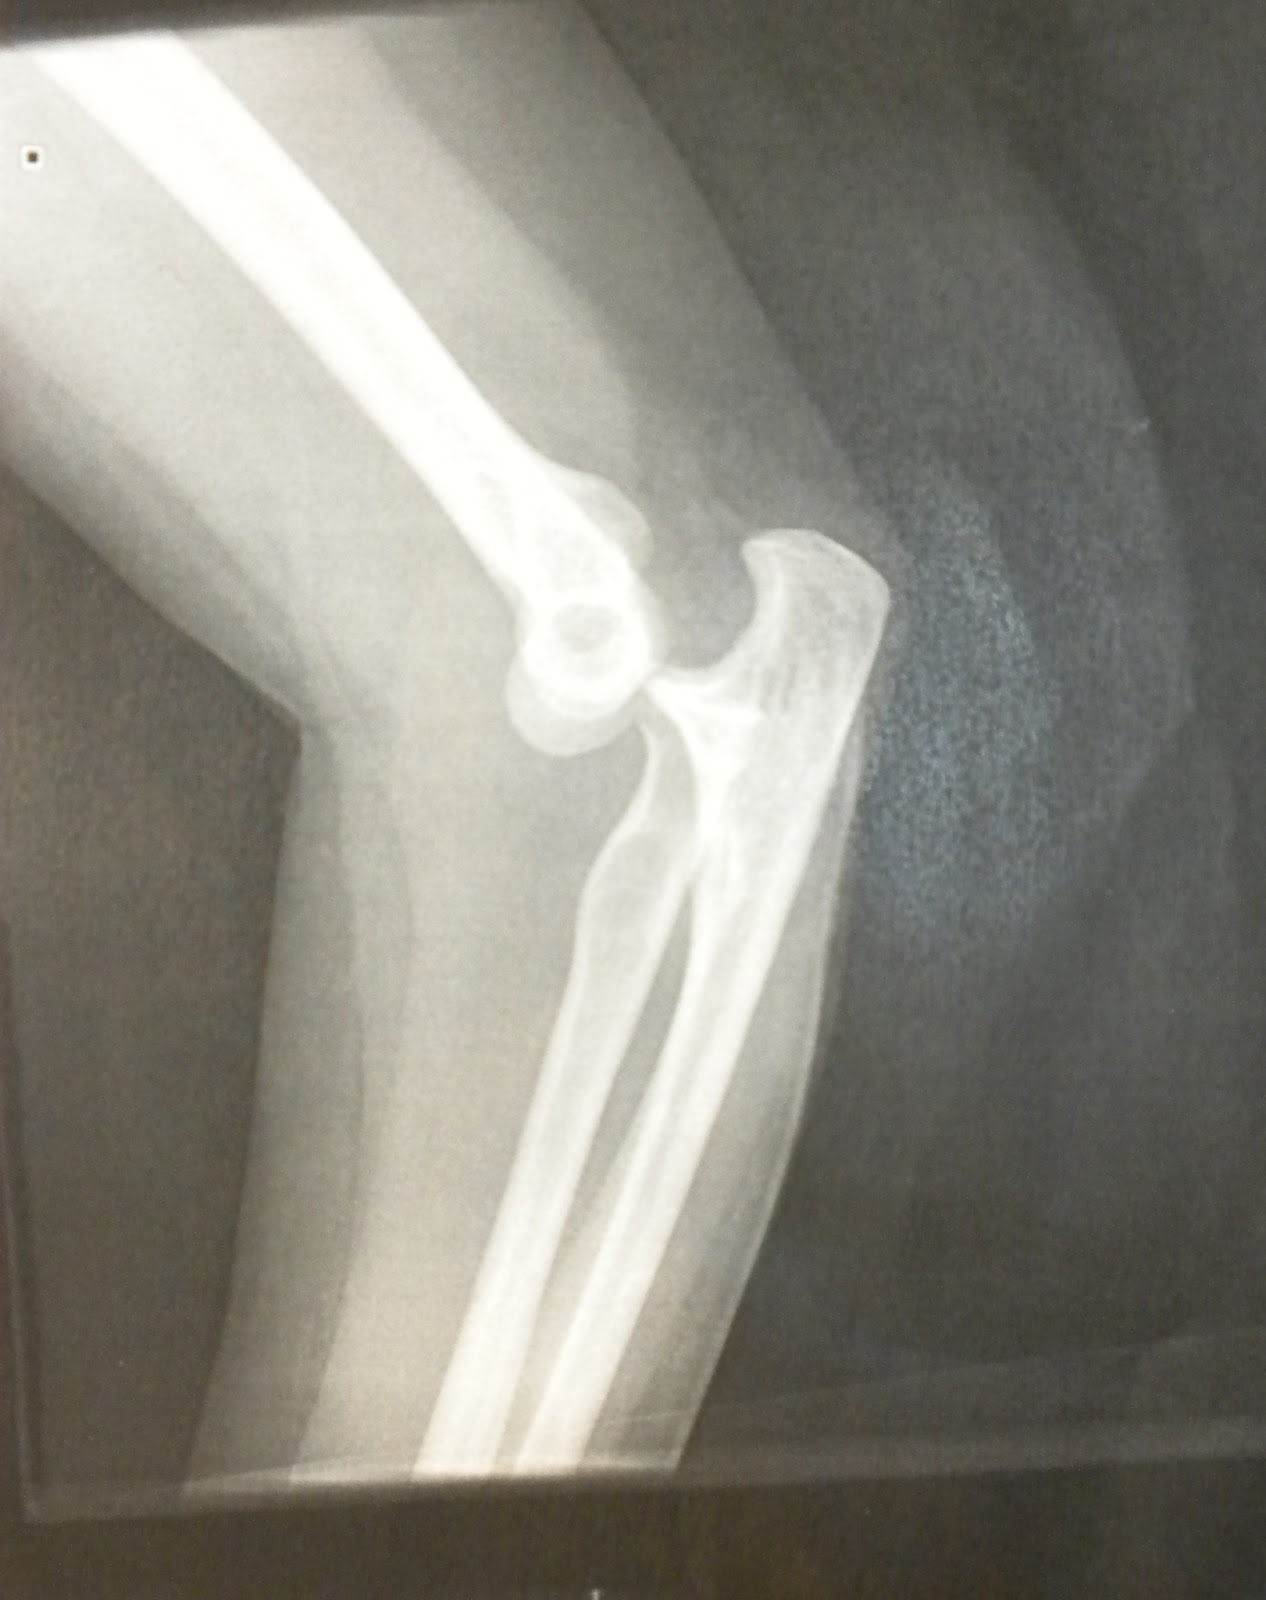

Here's the proof:

I asked Melissa the next day if I'd cried out at all during the procedure. "Are you sure you want to know?"